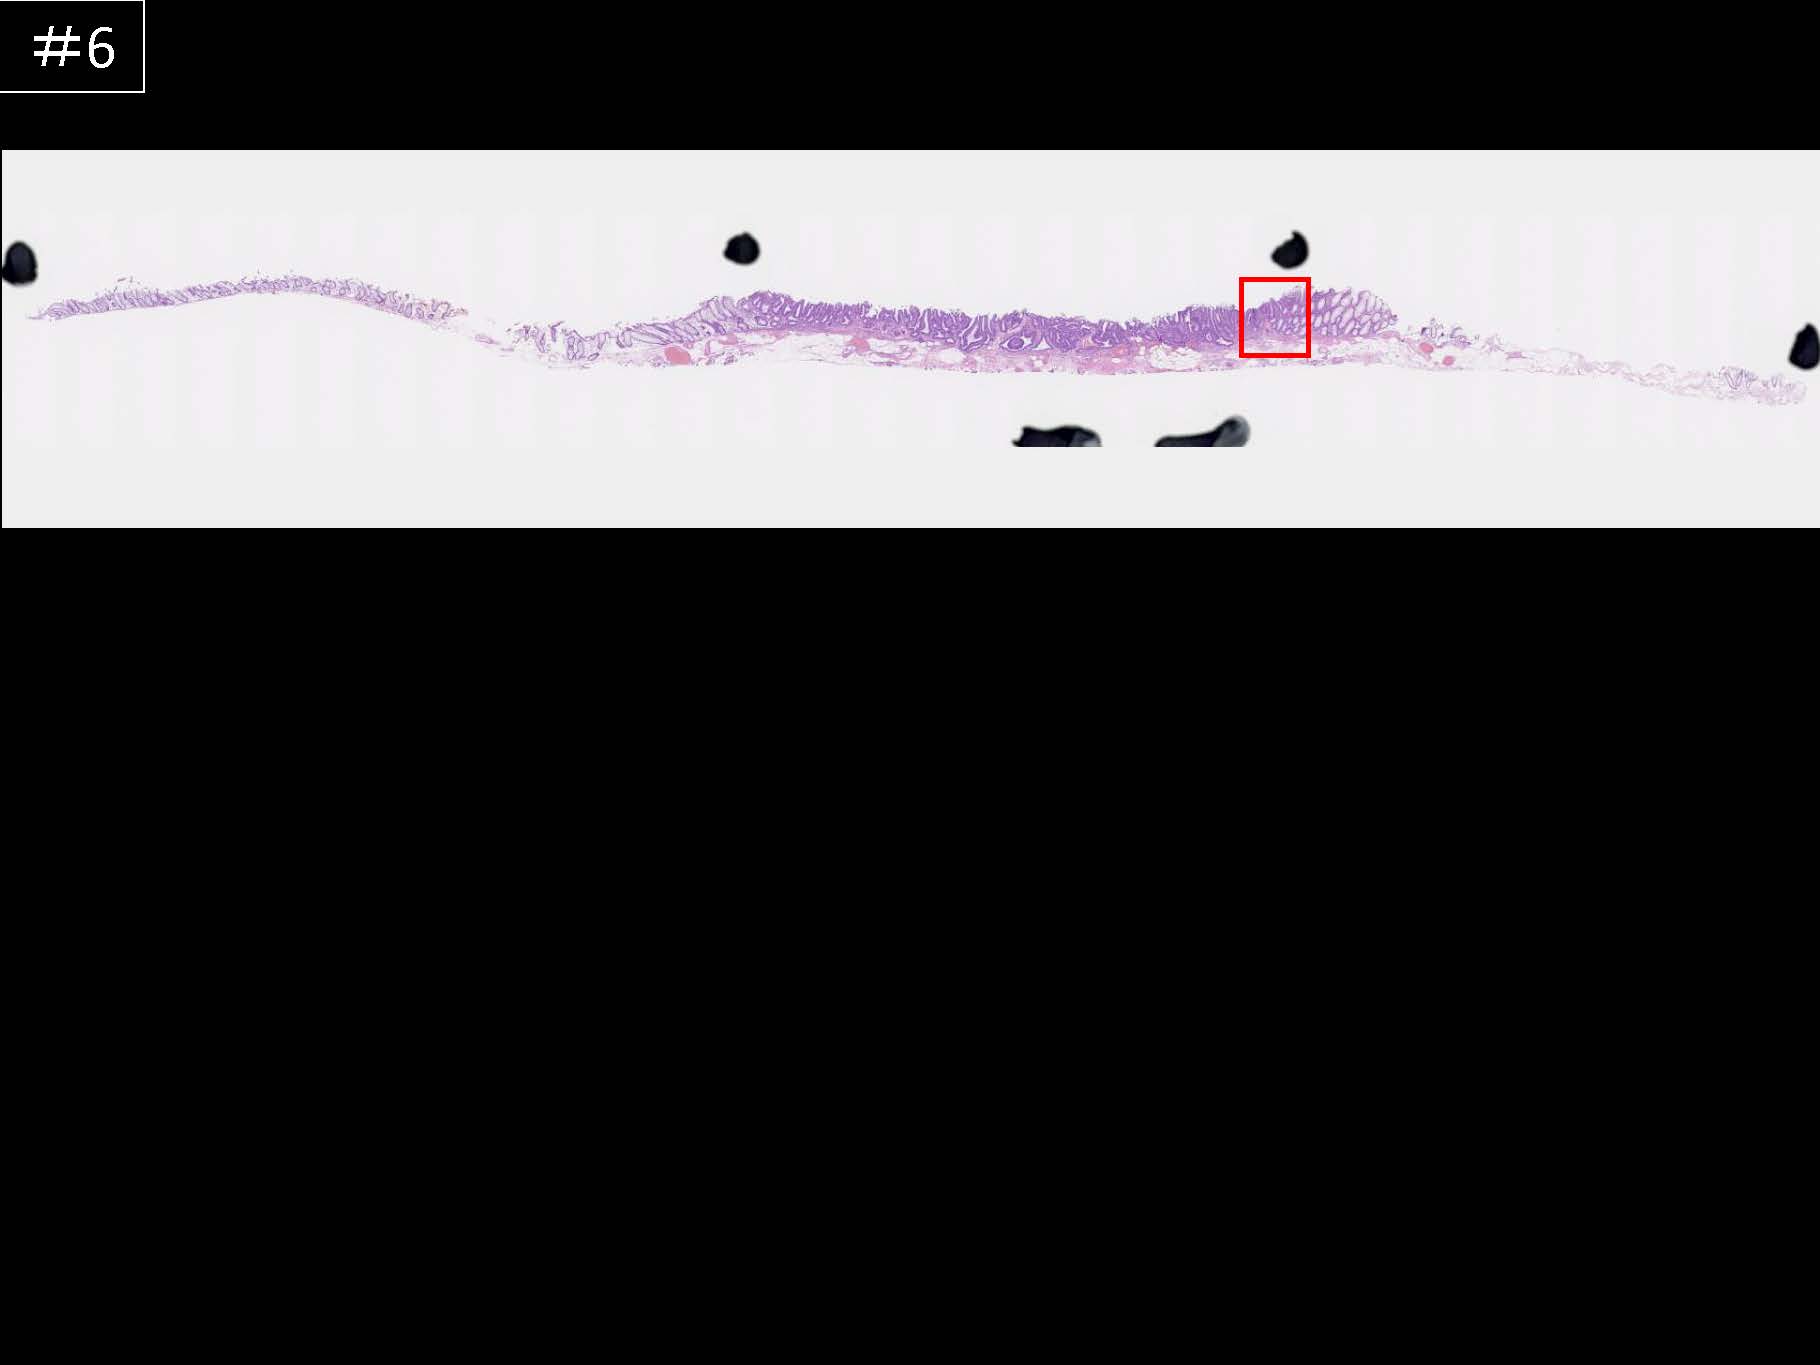

消化管Mapping~大腸~ 2021.10.27

消化管Mapping

消化管Mapping~大腸~

消化器内科

内視鏡検査・治療